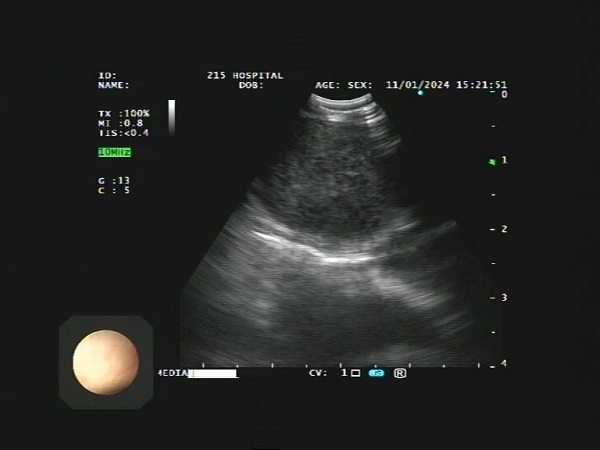

超声支气管镜引导下穿刺针吸活检术,是一种在超声支气管镜引导下经支气管壁穿刺针吸取得组织学标本的技术。超声支气管镜是在支气管镜前端安装有超声探头,利用超声技术能够清晰显示气管腔外的结构,准确区分肿物、淋巴结和血管等结构。

与常规支气管镜引导下穿刺针吸技术相比,超声支气管镜的应用,使操作者能够通过实时的超声图像确认需要穿刺的部位及穿刺针的位置、走向,有效避免穿刺到大血管的风险,既提高了穿刺的准确度,又能扩大适应症,降低风险。该项技术主要是针对肺门、纵隔占位性病变、淋巴结、肺结节病等进行经支气管穿刺针吸活检,取得组织标本进行病理学检查以明确诊断。